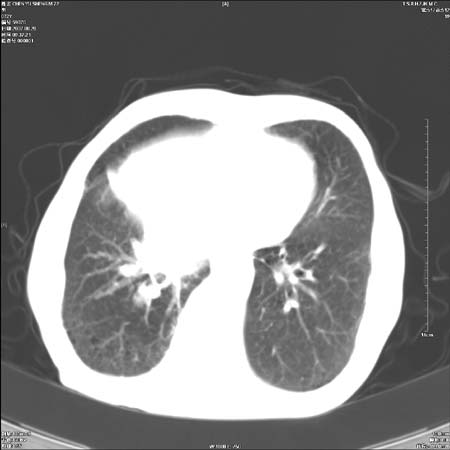

男性,72岁,既往肺结核,今复查。无前片对比。

右侧中央型肺癌伴中叶不张可能性大,建议增强扫描.右上肺陈旧性肺结核.慢性支气管炎伴肺气肿.右侧少量胸腔积液.

中心性肺癌肺转移

右侧中央型肺癌伴中叶不张可能性大,建议纤支镜检查.右上肺陈旧性肺结核.肺气肿。

典型右肺中心型肺癌

右侧中央型肺癌伴肺不张可能性大,建议增强扫描.右上肺陈旧性肺结核.慢性支气管炎伴肺气肿.右侧少量胸腔积液.

右肺中心型肺癌

右侧中央型肺癌.上肺陈旧性肺结核.

1右侧中央型肺癌伴中叶不张2右侧少量胸腔积液3右上肺陈旧性肺结核

1.右肺中心性肺癌并右肺中叶综合征2。右侧胸腔少量积液3。右肺上叶结核球已钙化,4。慢支伴肺气肿

右侧中央型肺癌伴中叶不张可能性大,建议纤支镜检查.右上肺陈旧性肺结核.肺气肿。

右侧中央型肺癌伴中叶不张可能性大,建议增强扫描.右上肺陈旧性肺结核.慢性支气管炎伴肺气肿.右侧少量胸腔积液.

右侧中央型肺癌伴中叶不张

右肺中央型肺癌伴右肺中叶不张。

右上肺陈旧性肺结核。

支持右肺中心型肺癌并中叶不张,右上肺陈旧性肺结核钙化,右侧少量胸腔积液。

支持右侧中央型肺癌伴中叶不张可能性大,建议增强扫描.右上肺陈旧性肺结核.慢性支气管炎伴肺气肿.右侧少量胸腔积液.

右侧中心型肺癌可能性大.肺气肿.胸腔积液.

支持 1右侧中心型肺癌伴中叶不张2右侧少量胸腔积液3右上肺陈旧性肺结核4双肺局限性肺气肿

1,右侧中央型肺癌.

2,右上肺陈旧性肺结核.

1.右侧中央型肺癌伴中叶不张,建议纤支镜检查.

2.右上肺陈旧性肺结核.

3.肺气肿。

4.右侧少量胸腔积液.

右侧中央型肺癌伴中叶不张并纵隔淋巴结增大,建议增强扫描.右上肺陈旧性肺结核.慢性支气管炎伴肺气肿.右侧少量胸腔积液。

右肺中心型肺癌并肺不张,陈旧性肺tb.慢支,肺气肿.

陈旧性肺结核.慢性支气管炎伴肺气肿,中央型肺癌伴中叶不张。

右侧中央型肺癌伴中叶不张可能性大;右上肺陈旧性肺结核.慢性支气管炎伴肺气肿

陈旧性结核是存在,但真正致命的却是右侧中心型肺癌。